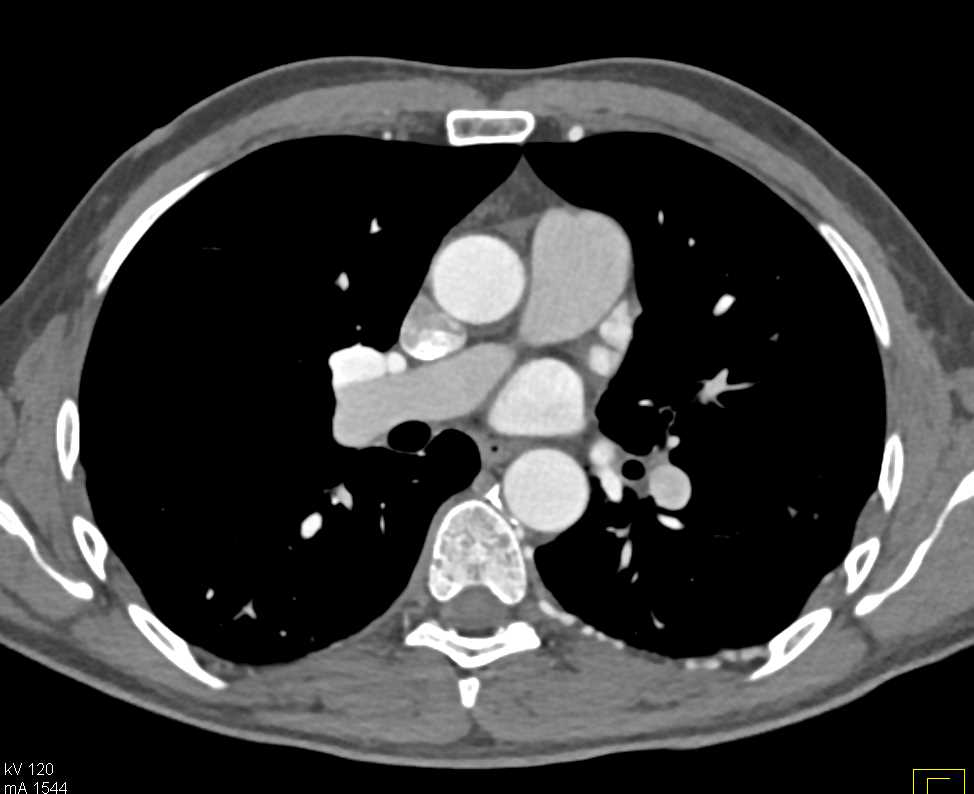

Osteomyelitis T-Spine